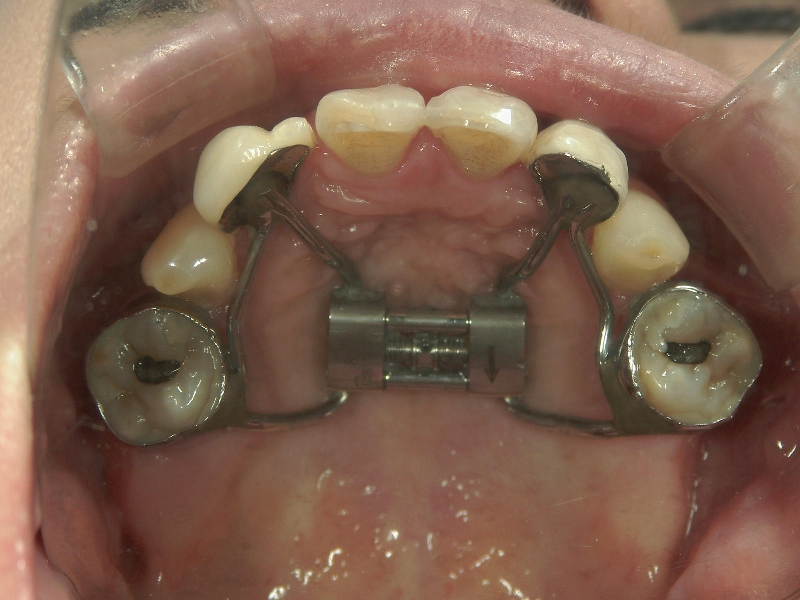

● 上顎骨の拡大

上顎(口蓋の部分)の骨に、外科手術で切れ目を入れて左右のあごのつなぎ目を切り離すことで、上顎の拡大が難しい成人の方もスムーズに広げることが可能です。